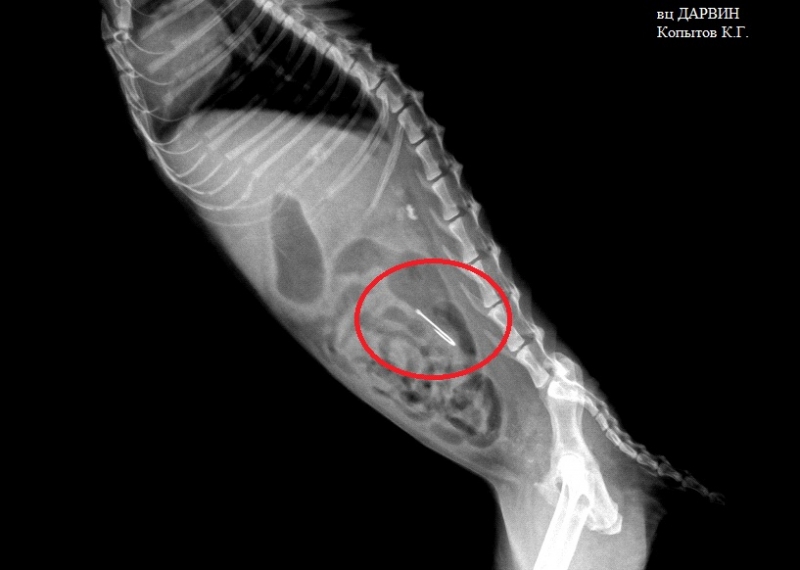

Иголка

Металл также является рентгеноконтрастным предметом с характерной узнаваемой формой.

Рентгенограмма брюшной полости (рентген) собаки, которая съела несколько гвоздей, которые вы можете видеть в ее желудке.